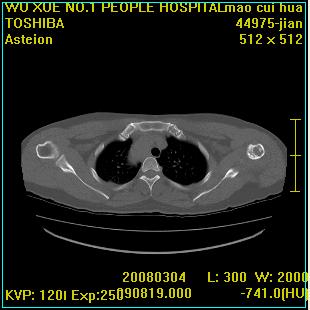

标题: CT12025:男,50岁,左肩活动受限半年。 [打印本页]

标题: CT12025:男,50岁,左肩活动受限半年。

能有x线平片就好了。肱骨头骨结构有破坏。

肩关节骨质破坏呈小囊状,其周软组织轻度肿胀,余未见异常。

考虑:肩袖损伤。建议mri。

左侧肱骨头密度不均匀,高低混杂,周围软组织略肿胀,考虑结核性病变。

考虑左侧肱骨慢性骨髓炎。

左侧肱骨头密度不均匀,高低混杂,髓腔密度稍高,周围软组织略肿胀,肌间隙模糊,考虑慢性骨髓炎可能。密切结合临床!